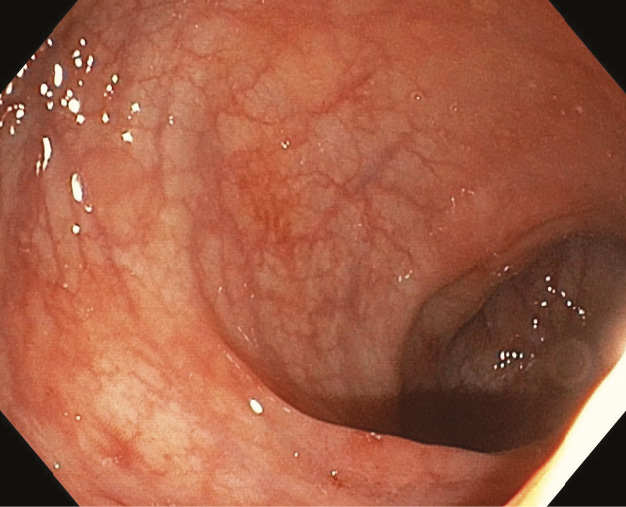

Илеоколоноскопия проводилась 67 пациентам с постковидным поражением кишечника. Наблюдали различные варианты эндоскопической картины. У 12 пациентов (17,9%) она соответствовала псевдомембранозному колиту (рис. 1А, Б), у 11 больных (16,4%) – очаговому геморрагическому колиту (очаги геморрагий разного размера на фоне гиперемированной слизистой при смазанном или сохраненном сосудистом рисунке) (рис. 2). У 2 больных (3%) впервые выявлена эндоскопическая картина язвенного колита умеренной и высокой активности (рис. 3А, Б). Эрозии, единичные или множественные, диагностированы у 19 (28,4%) пациентов (рис. 4). У части больных эндоскопия не выявила значимых макроскопических изменений и дефектов слизистой оболочки. Так, у трети пациентов (n = 21, 31,3%) слизистая оболочка толстой кишки или практически не отличалась от нормы (рис. 5), или наблюдались минимальные воспалительные изменения (отсутствие сосудистого рисунка, гиперемия, незначительная ранимость слизистой) даже при выраженном диарейном синдроме (рис. 6). В 2 случаях (3%) при клинически значимом профузном кишечном кровотечении эндоскопически отмечалась выраженная спонтанная кровоточивость слизистой оболочки на всем протяжении толстой кишки (рис. 7А, Б). Никакого локального источника кровотечения при этом обнаружено не было.

Рис. 5. Неизмененная слизистая оболочка толстой кишки с усилением сосудистого рисунка у больного с интенсивной диареей, лихорадкой и повышением С-реактивного белка после перенесенной инфекции SARS-CoV-2

Рис. 6. Минимальные воспалительные изменения слизистой оболочки толстой кишки (очаговая гиперемия, усиленный сосудистый рисунок, единичные мелкие геморрагии) у больного с диареей и лихорадкой после перенесенной инфекции SARS-CoV-2

6. Fig. 5. Unchanged colonic mucosa with enhanced vascular structures in a patient with severe diarrhea, fever and increased C-reactive protein after the SARS-CoV-2 infection

7. Fig. 6. Minimal inflammatory abnormalities in the colonic mucosa (focal hyperemia, enhanced vasculature, single small hemorrhages) in a patient with diarrhea and fever after the SARS-CoV-2 infection